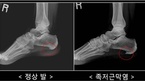

주부 장희정(여·32)씨는 플랫슈즈를 즐겨 신는다. 하이힐이 발 관절 건강에 안 좋다는 얘기를 들은 후부터다. 마트에서 장을 보거나 아이와 외출할 때는 물론이고 예전 같았으면 하이힐을 꼭 신었을 차려입어야 하는 자리에도 플랫슈즈만을 고집했다. 하지만 며칠 전